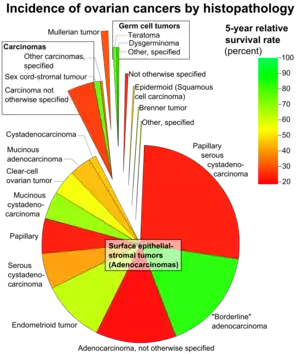

Endometrioid tumors are a class of tumors that arise in the uterus or ovaries that resemble endometrial glands on histology.[1] They account for 80% of endometrial carcinomas[1]: 724 and 20% of malignant ovarian tumors.[1]: 728

Ovarian endometrioid tumors are part of the surface epithelial tumor group of ovarian neoplasms (10–20% of which are the endometrioid type). Benign and borderline variants are rare, as the majority are malignant. There is an association with endometriosis and concurrent primary endometrial carcinoma (endometrial cancer).